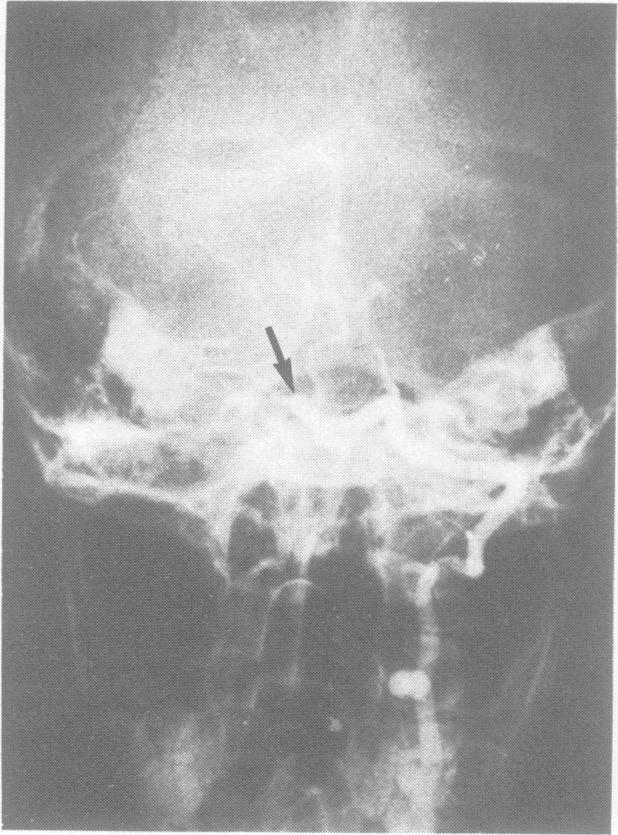

Occlusion of the basilar artery in a 7 year old boy.

J Neurol Neurosurg Psychiatry. 1987 Apr;50(4):494-5. doi: 10.1136/jnnp.50.4.494.

https://cdn.ncbi.nlm.nih.gov/pmc/blobs/d1ad/1031894/698f61cd9b71/jnnpsyc00551-0120-a.jpg